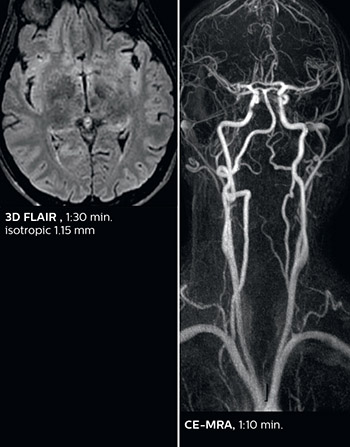

A two year follow-up scan of a CPA meningioma using both Ingenia 3.0T without CS and Ingenia Elition 3.0T with Compressed SENSE allows for a nice comparison to demonstrate the protocol improvements achieved on the Elition: 3D FLAIR has a shortened scan time, improved SNR and still the same spatial resolution. BrainView (3D T1 TSE) has improved spatial resolution and SNR with shortened scan time. For 3D T2 Drive the spatial resolution has been improved. 3D THRIVE used to have an interpolated 0.8 mm slice thickness, but true thickness at 1.6 mm, so that axial slices displayed a decent quality, but reformats were suboptimal.

Compressed SENSE is used on Elition to improve spatial resolution and reduce the non-interpolated slice thickness to allow smoothly reformatted images. Total scan time (adding SmartBrain and an additional b2000 diffusion) was 13:19 on Ingenia, and is now reduced to 10:42 on Ingenia Elition.

Ingenia 3.0T (without Compressed SENSE)

3D FLAIR (without Compressed SENSE)

3D FLAIR

1.0 x 1.0 x 1.0 mm*

4:24 min.

3D TSE T1w (without Compressed SENSE)

3D TSE T1w

1.0 x 1.0 x 1.2 mm*

2:40 min.

3D T2w Drive (without Compressed SENSE)

3D T2w Drive

0.8 x 0.8 x 1.0 mm*

3:05 min.

3D T1w THRIVE (without Compressed SENSE)

3D T1w THRIVE

0.8 x 0.8 x 1.6 mm*

1:30 min.

Ingenia Elition 3.0T with Compressed SENSE

3D FLAIR (with Compressed SENSE)

2:50 min.

3D TSE T1w (with Compressed SENSE)

2:10 min.

3D T2w Drive (with Compressed SENSE)

0.7 x 0.7 x 0.7 mm*

2:52 min.

3D T1w THRIVE (with Compressed SENSE)

0.7 x 0.7 x 0.8 mm*

*true voxel size, without interpolation